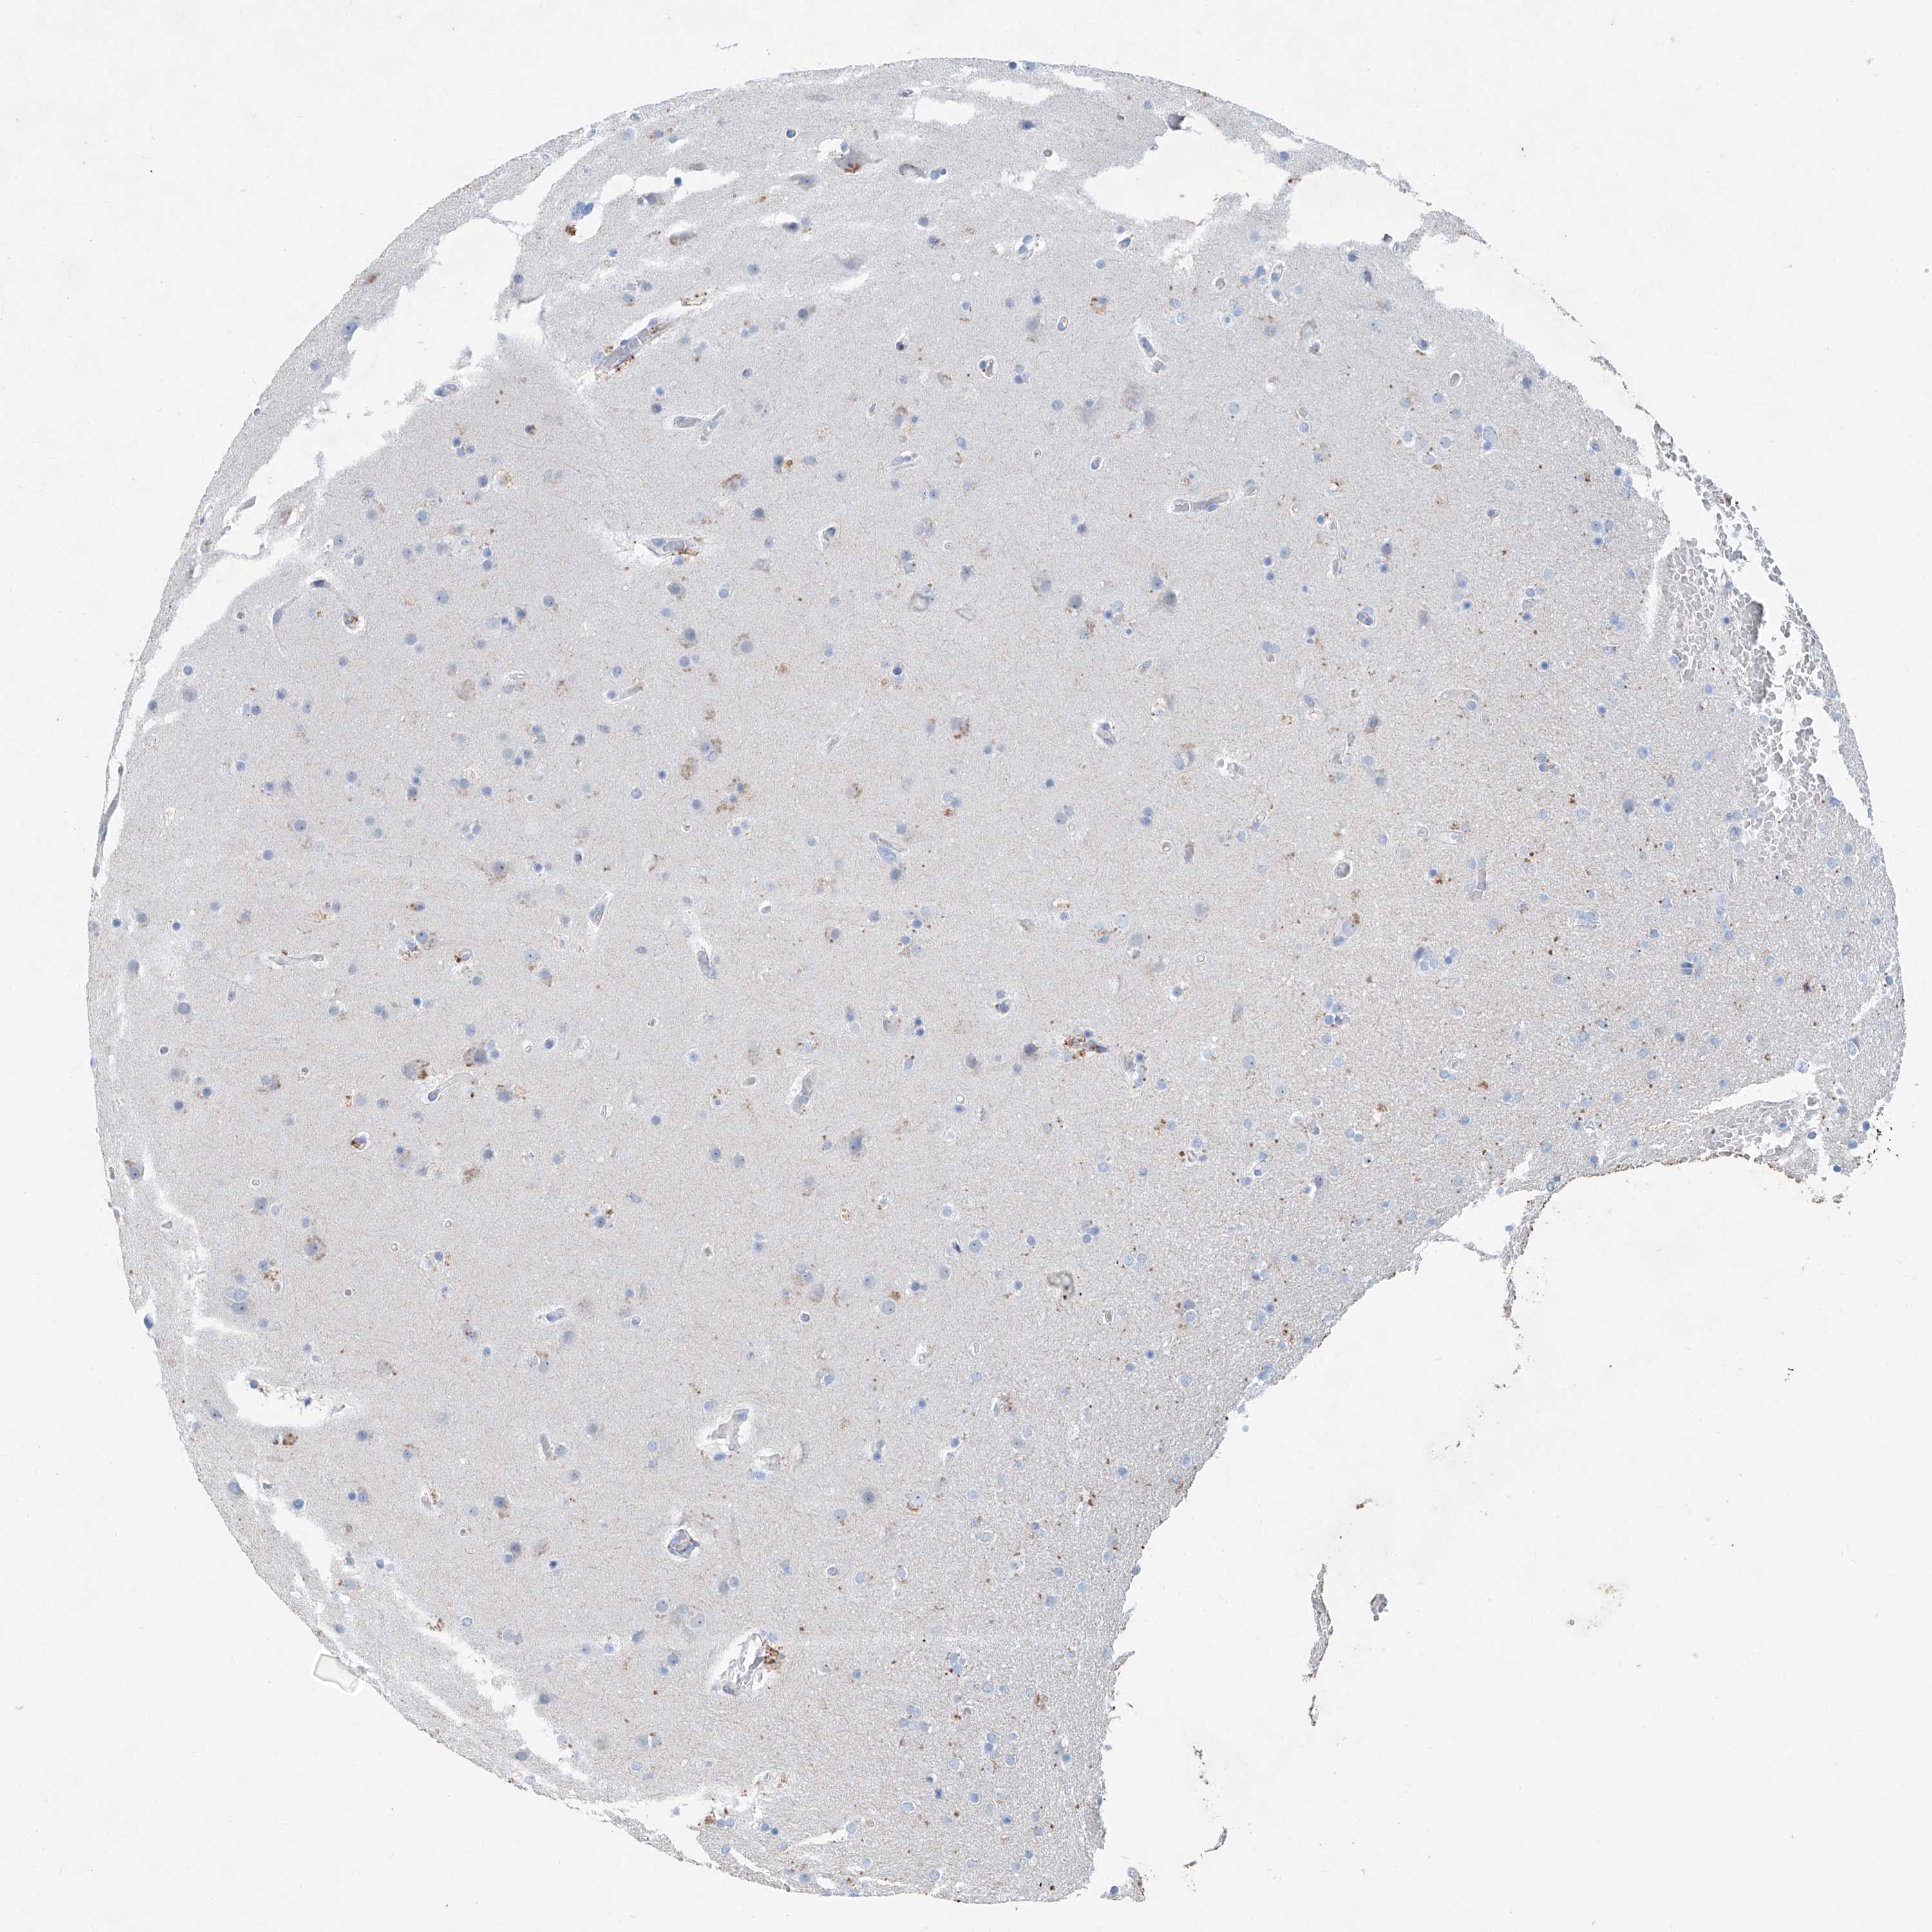

GLIOMA - Protein expressioni

A mouse-over function shows sample information and annotation data. Click on an image to view it in a full screen mode. Samples can be filtered based on level of antibody staining by selecting one or several of the following categories: high, medium, low and not detected. The assay and annotation is described here.

Note that samples used for immunohistochemistry by the Human Protein Atlas do not correspond to samples in the TCGA dataset.

Antibody stainingi

Antibody staining in the annotated cell types in the current human tissue is reported as not detected, low, medium, or high, based on conventional immunohistochemistry profiling in selected tissues. This score is based on the combination of the staining intensity and fraction of stained cells.

Each image is clickable and will lead to virtual microscopy that enables deeper exploration of all samples and also displays staining intensity scores, fraction scores and subcellular localization as well as patient and tissue information for each sample.

Antibody HPA029642

Antibody HPA029643

Glioma, malignant, High grade

Glioma, malignant, Low grade